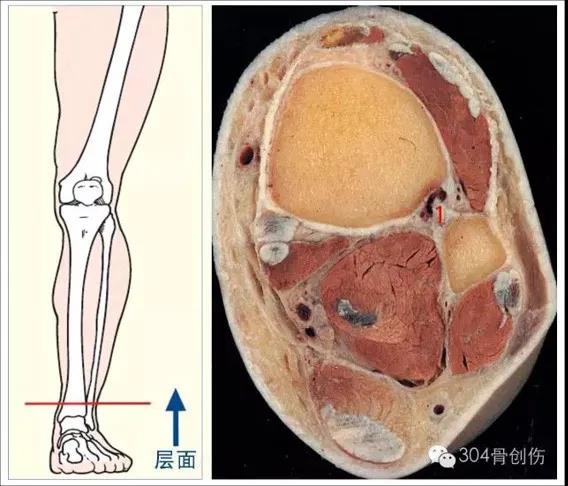

踝关节解剖